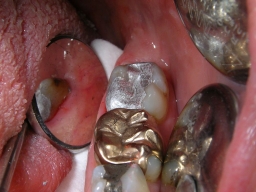

| Im Frontzahnbereich sind die weißen Kompositfüllungen natürlich das Mittel der Wahl. Auch kleine Füllungen, inbesondere in den vorderen, besonders sichtbaren, kleinen Backenzähnen, lassen sich mit Composite gut versorgen. Generell gilt: Je größer die Füllung, desto größer wird der Haltbarkeitsvorsprung für Amalgam. Die ästhetische und über Jahrzehnte haltbare Alternative zu großen Amalgamfüllungen sind deshalb nicht große Kunststofffüllungen, sondern keramisch verblendete Kronen, die problemlos auf die mit Amalgam sanierten Backenzähne zementiert werden können: | ||||||||||||||||||||||||||||||||||||||||||||||||||||||||||||||||||||||||

![]() |

![]() | |||||||||||||||||||||||||||||||||||||||||||||||||||||||||||||||||||||||

| Die Patientin wünschte eine dauerhafte, weiße Versorgung. | ||||||||||||||||||||||||||||||||||||||||||||||||||||||||||||||||||||||||